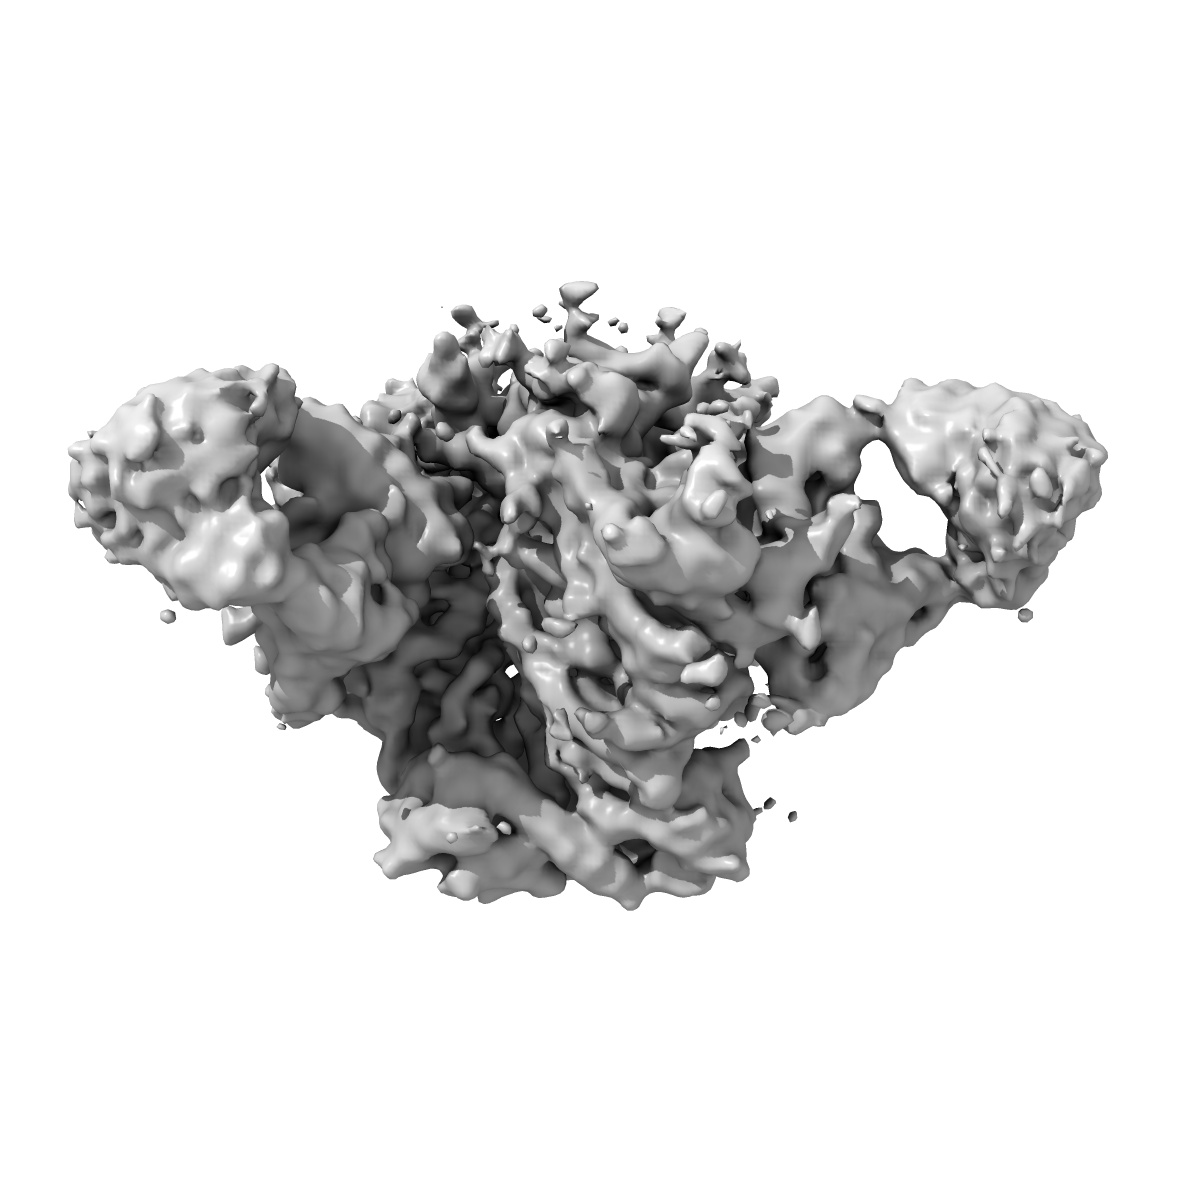

CryoEM structure of VRC01-CH848.0358.80

Single-particle4.9 Å

Sample: VRC01-CH848.0358.80

Structural basis for breadth development in the HIV-1 V3-glycan targeting DH270 antibody clonal lineage.

(2023) Nat Commun , 14 , 2782 - 2782